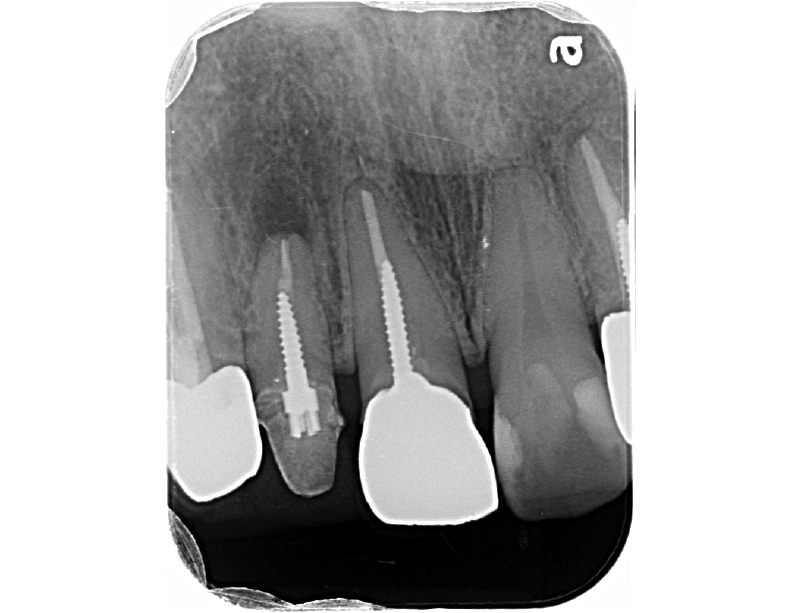

根管治療後のレントゲン写真です。

根管治療後のCTです。

歯根の周囲の骨吸収もだいぶ改善されました。